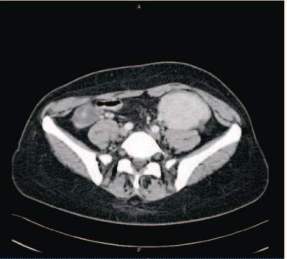

Obrázky 1 a 3 ukazují nález octreoscanu před operací a po radikální operaci, obrázky 2 a 4 ukazují totéž na CT. Obrázek 5 demonstruje echokar biografický nález významné trikuspidální regurgitace, obrázek 6 ukazuje normalizaci onkomarkerů sérového chromograninu A a obrázek 7 normalizaci hodnot odpadů 5 - hydroxyindoloctové kyseliny (5 - HIOK) v moči. Hodnoty CA 125 byly v celém průběhu v normě.

CT ukazující velký karcinoid levého ovaria - před operací